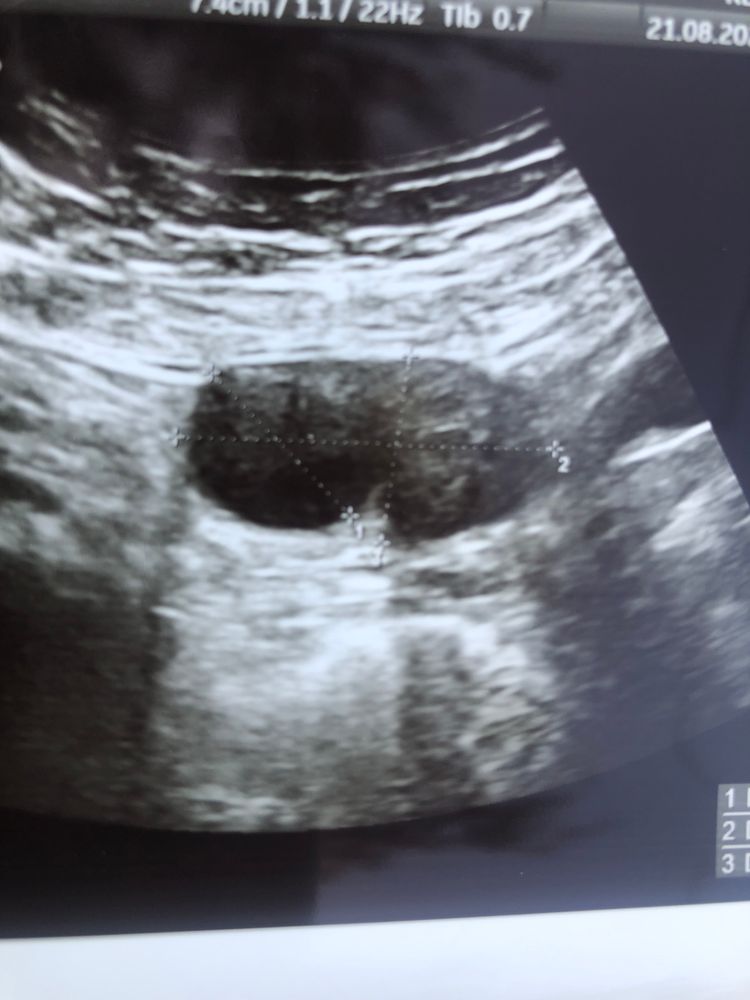

вот фото фолликула , тут видно что началась овуляция ? Какой-то другой он ,да? Может по фолликулу она поняла что началась овуляция?

Обычно перед О фолики форму меняют. Да и размер у фолика уже вполне себе нормальный чтоб лопнуть. После выхода яйцеклетки тесты не могут показывать. Тесты показывают не саму О , а только скачок гормона ЛГ который идёт перед О(в среднем за 12-24 часа до О). Так что вполне реально , что вы просто пропустили его. У меня один раз этот пик был максимум часа 1.5-2.. И если бы меня не переклинило и я бы не сделала тест через час после первого , то я бы все пропустила. Так что откладывайте тесты, берите мужа в охапку и вперед работать. Желательно сегодня и завтра. Потом денька через 3-5 сходите на узи , чтоб жт посмотрели